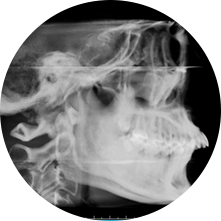

首先,需要拍攝牙齒照片、X光片并進行掃描/取模,一遍據(jù)此制定治療方案